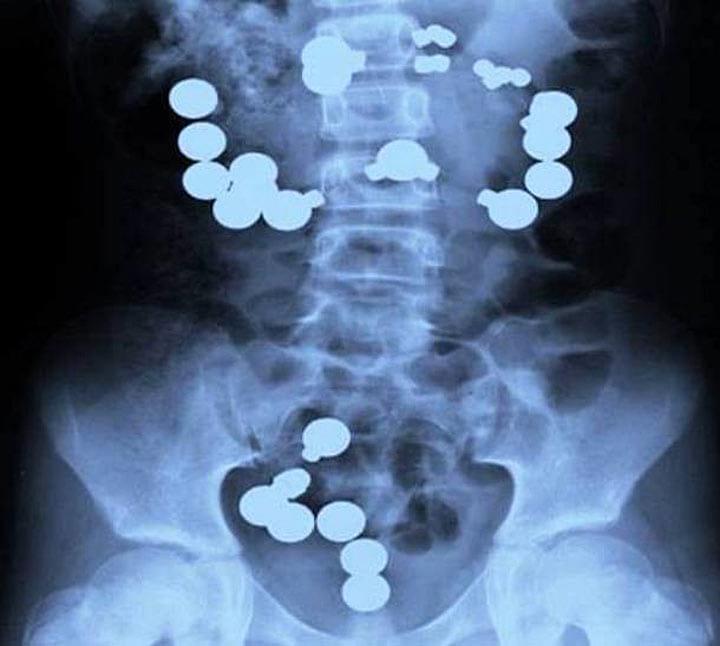

8. Ребенок перепутал разноцветные металлические шарики с конфетами и съел их